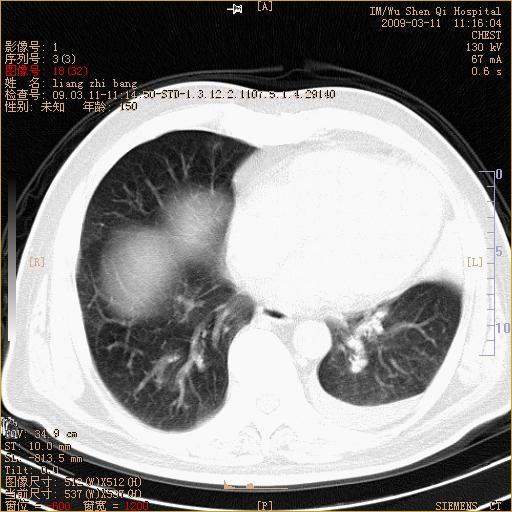

标题: CT18604:男,60岁,咳嗽一月余 [打印本页]

标题: CT18604:男,60岁,咳嗽一月余

1)考虑左肺上叶中央型肺癌并左肺上叶肺不张;建议必要时行纤支镜检查进一步明确诊断。2)左侧胸腔积液。

肺门肿块、支气管开口闭塞伴肺不张及胸水!典型的中心型肺癌变现!

1、左肺上叶中央型肺癌并上叶阻塞性肺不张。

2、左侧胸腔少量积液,右侧胸膜轻度增厚。

左肺们肿块并左肺上叶不张。考虑左肺中心性肺癌并左肺上叶不张及左侧胸腔积液